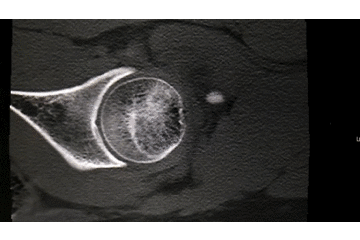

辅助检查:CT 检查提示右侧股骨颈骨皮质不连续,可见透亮骨折线及碎骨片影,断端错位、成角,周围软组织肿胀;右侧髋臼后下缘及左侧耻骨上支骨皮质不连续,断端未见明显错位;右侧髋臼后缘见类圆形稍低密度影,大小约 5*9 mm,边界清楚,边缘见硬化边;右侧髋关节在位,关节间隙未见明显变窄。

初步诊断:右股骨颈骨折(经颈型)